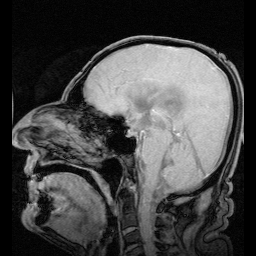

登录/注册后可看大图

图片来源:Pixabay